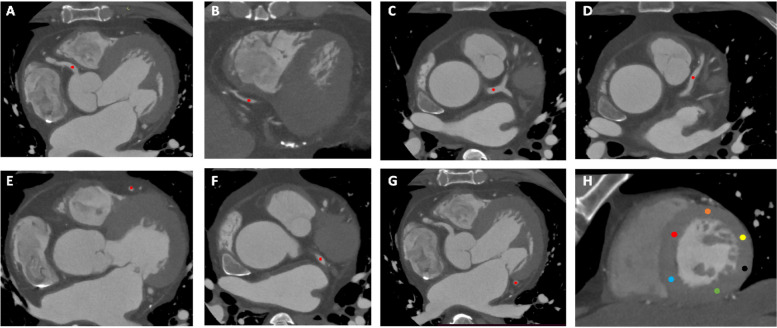

Methods: Sixty-three patients (mean age, 61 ± 11 years; range, 18-81 years; 40 men) who had undergone coronary CT angiography between June and October 2022 were retrospectively included. Image noise, signal to noise ratio, and contrast to noise ratio were quantified in both proximal and distal segments of the major coronary arteries. The left ventricle myocardium contrast homogeneity was analyzed. Two independent reviewers scored overall image quality, image noise, image sharpness, and myocardial homogeneity.

Results: Image noise in Hounsfield units (HU) was significantly lower (P < 0.001) for the SR-DLR (11.2 ± 2.0 HU) compared to those associated with other image reconstruction methods including FBP (30.5 ± 10.5 HU), hybrid IR (20.0 ± 5.4 HU), and DLR (14.2 ± 2.5 HU) in both proximal and distal segments. SR-DLR significantly improved signal to noise ratio and contrast to noise ratio in both the proximal and distal segments of the major coronary arteries. No significant difference was observed in the myocardial CT attenuation with SR-DLR among different segments of the left ventricle myocardium (P = 0.345). Conversely, FBP and hybrid IR resulted in inhomogeneous myocardial CT attenuation (P < 0.001). Two reviewers graded subjective image quality with SR-DLR higher than other image reconstruction techniques (P < 0.001).

Conclusions: SR-DLR improved image quality, demonstrated clearer delineation of distal segments of coronary arteries, and was seemingly accurate for quantifying CT attenuation in the myocardium.